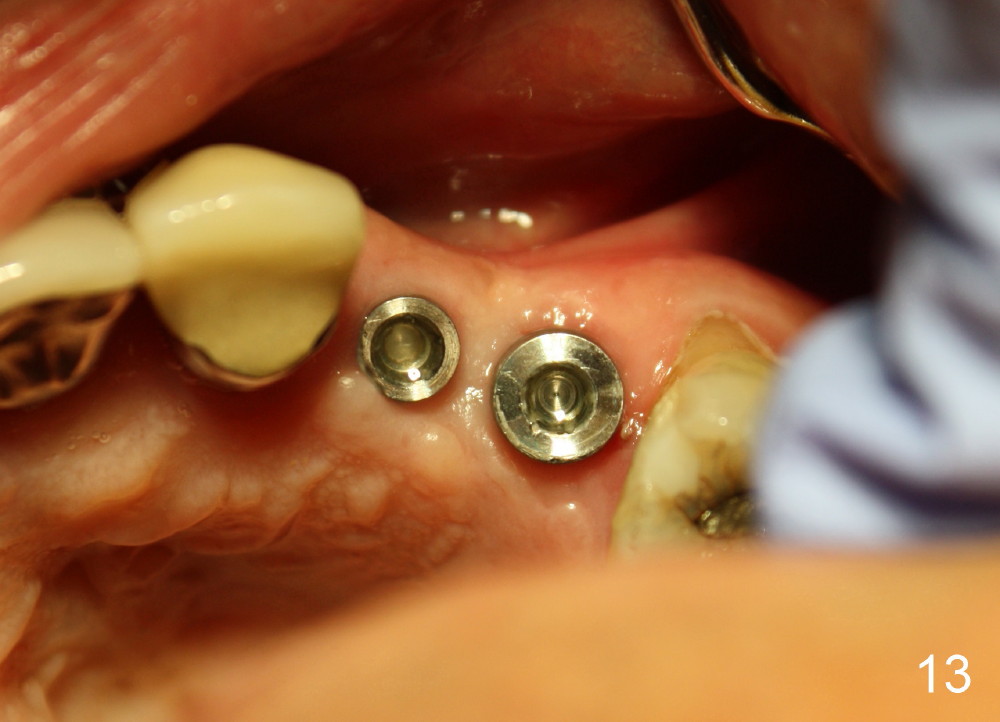

Three month follow-up shows that the gingiva and bone heal around these two implants (Fig.13-15). Crowns are cemented 4.5 months postop (Fig.16). There is no or minimal bone loss 9 months post cementation (Fig.17, as compared to Fig.15). The bone is stable around the implants 18 months post cementation (Fig.18 panoramus). Root canal therapy is done at #14 between the last follow up appointments.